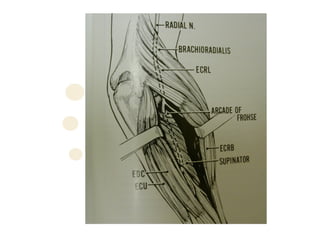

Posterior Interosseous Nerve

• Gains access to posterior forearm by diving

posterior and laterally through ligament of

Frohse and the interval between the two

heads of supinator

• Arcade of Frohse is a fibrous arch originating

lateral epicondyle superior part of superficial

layer of supinator

– German Anatomist, Fritz Frohse (1871-1916)

Radial Tunnel Syndrome

1. Fibrous bands

•   Tight fibrous bands anterior to radial head at entrance of

tunnel

1. Arcade of Frohse

•   Most common

1. Leash of Henry

•   Radial recurrent vx that fan out over radial nn

1. Medial border of ECRB